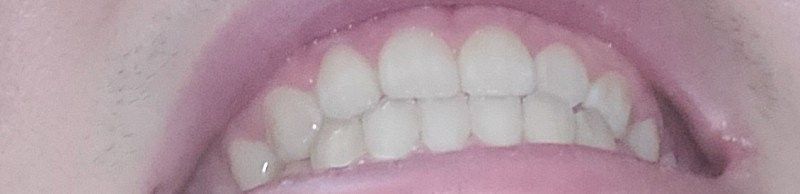

앞니 아랫니 포개긴하는데 덜 포개는 느낌이 들어요

겨우 포개는 느낌적인 느낌?

원래좀더 윗치아들이 앞으로 조금더 나와야하지 않나 그렇게 생각합니다

윗치아들이 덜 나온건지 아랫치아들이 많이 나온건지 모르겠어요

윗니가 앞으로 나오는 정도는 사람마다 다릅니다. 지금 사진상으로 보아 윗니가 앞으로 나온 양이 조금 적어 보이나

정상 범위입니다. 다만 오른쪽 작은 앞니(측절치)는 아랫니가 앞으로 나온 반대교합 입니다.